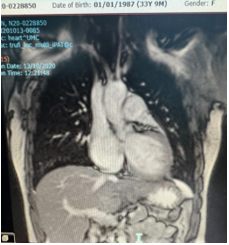

Chụp cộng hưởng từ tim có tiêm tương phản từ (MRI): Chức năng tâm thu thất trái giảm (EF= 27,9%). Dãn thất trái. Giảm động các thành thất. Ghi nhận có tăng sinh lớp cơ bè ở thành trước, thành bên, thành dười vùng giữa và vùng mỏm tạo thành các khe sâu, tỉ lệ cơ bè/ cơ tim lớn nhất ở thành bên vùng giữa #2,3, gợi ý bệnh cơ tim xốp. Chức năng tâm thu thất phải giảm (EF=28,8%).

Hình 1. Hình ảnh chụp cộng hưởng từ tim trường hợp 1

III.2. Hai trường hợp báo cáo: đều là bệnh nhân nữ, trẻ tuổi, với triệu chứng lâm sàng gợi ý của suy tim. Qua tầm soát bệnh lý tim mạch cho thấy cả hai trường hợp có kết quả siêu âm tim là giãn buồng thất trái và phân suất tống máu thất trái (EF) giảm hướng nghĩ đến bệnh cơ tim giãn. Tuy nhiên, nguyên nhân bệnh lý cơ tim giãn ở cả 2 trường hợp cần phải được xác định để có thể theo dõi và điều trị tốt hơn. Kết quả trên chụp cộng hưởng từ có tiêm tương phản từ đã cho kết quả chẩn đoán bệnh cơ tim thể xốp tâm thất trái (trường hợp 1) và cả hai tâm thất trái – tâm thất phải (trường hợp 2) với tiêu chuẩn tỷ lệ cơ bè/ cơ tim bằng 2,3 và 3,3 kèm theo suy chức năng thất trái nặng EF = 28,8% và 38,34% tương ứng với trường hợp 1 và trường hợp 2. Như vậy, chẩn đoán bệnh cơ tim thể xốp thất trái trên bệnh nhân được xác định chủ yếu dựa vào kết quả siêu âm tim gợi ý bệnh cơ tim giãn và kết quả chụp cộng hưởng từ có tiêm tương phản từ cho chẩn đoán xác định nguyên nhân với biến chứng suy tim phân suất tống máu giảm. Trường hợp 2 là một bệnh cảnh hiếm gặp của bệnh cơ tim thể xốp khi tổn thương ghi nhận ở cả hai tâm thất phải và trái. Điều trị kiểm soát biến chứng suy tim với phác đồ điều trị 4 thuốc theo khuyến cáo của Hội tim Châu Âu [10] và Bộ Y tế [11] cho thấy bệnh nhân đáp ứng tốt với điều trị. Bệnh nhân vẫn đang được theo dõi định kỳ tại Khoa Khám bệnh – Bệnh viện Đại học Y Dược Tp. Hồ Chí Minh, tiếp tục đánh giá đáp ứng điều trị suy tim, theo dõi và điều trị kịp thời các biến chứng khác có thể xảy ra.